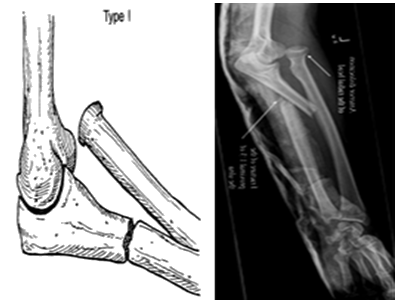

孟氏(Monteggia)骨折尺骨上1/3骨干骨折合并桡骨小头脱位

孟氏(Monteggia)骨折